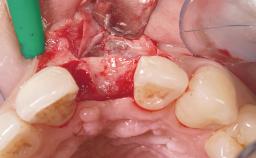

Immediate Placement of an Implant in a Maxillary Left Central Incisor Site

A 33-year-old female patient presented with an upper left central incisor that required extraction after a failed endodontic therapy. The tooth had been traumatized when the patient was a teenager and had undergone several endodontic treatments, including two apicectomy procedures. The patient was in good health and did not smoke. Clinical examination showed that the patient had a high lip line. In full smile, the gingival margins of the upper teeth were visible to the first molars. The gingival margins of central incisors 11 and 21 were only just showing. Examination of tooth 21 confirmed that the tooth was mobile and had hypererupted by 1 mm.

Placement Protocol Immediate implant placement

Tooth Site Maxillary incisor or canine

Socket Morphology Single-root socket

Socket Integrity Damage to one or more bone walls

Bone Volume Damage to one or more socket walls